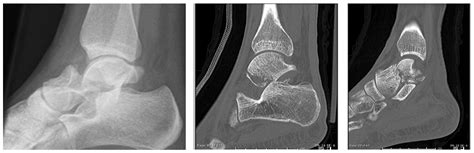

To determine the severity of a shattered talus bone, orthopedic surgeons rely on high-resolution imaging. Standard X-rays provide the initial view, but they are rarely enough to see the full extent of a comminuted fracture. A CT scan is almost always required to map out the fragments in 3D, allowing the surgeon to plan the reconstruction. MRI scans may also be used to evaluate the health of the soft tissues and the status of the blood supply to the bone fragments.

CT Scan Detailed mapping of bone fragments and joint surface damage.